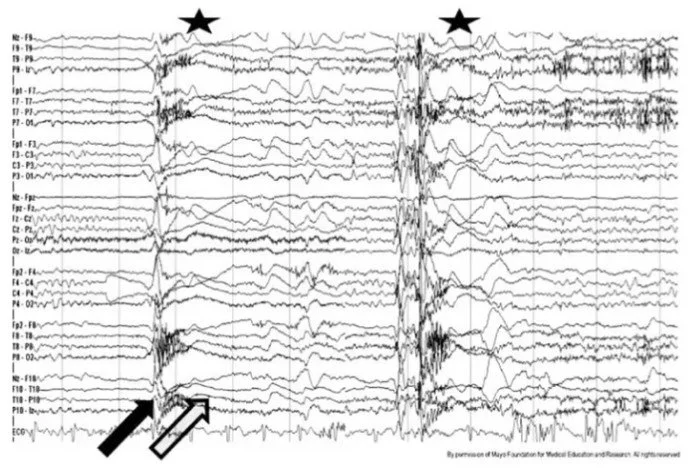

An electroencephalogram (EEG) is used to detect abnormalities in brain waves or electrical activity of the brain. EEG’s can be used to detect seizure activity in the brain as it will appear as spike-and-wave discharges on the EEG. The spike-and-wave discharges on the EEG result from synchronized bursts of neuronal firing that occur during a seizure. However, the sensitivity for an EEG to identify a seizure is less than 50% and therefore, a normal EEG does not rule out the possibility that the patient did not have a seizure.

Figure 1: EEG of a Tonic Seizure.